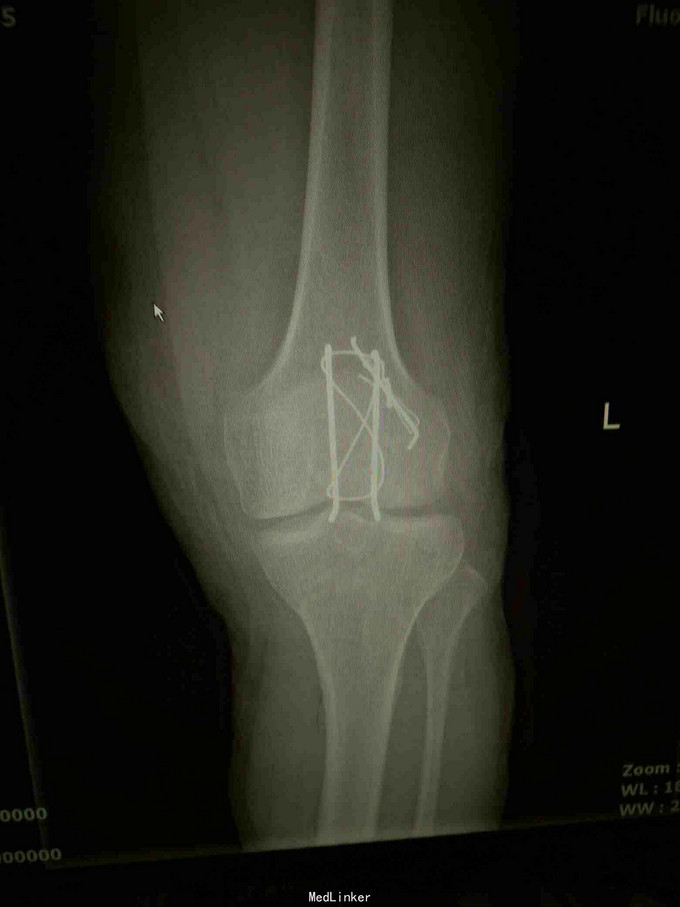

左髌骨粉碎性骨折

摔伤致左膝疼痛肿胀,活动受限1小时; 患者摔伤导致左膝疼痛,肿胀,活动受限,无皮肤破溃,无活动性出血,无晕厥等。

查体:左下肢活动受限,背伸障碍,左膝关节明显肿胀,压痛,扪及骨擦感,左足感觉及血循环可。 x片:左髌骨骨折。

诊断:左髌骨粉碎性骨折; 治疗,石膏固定,消肿止痛,行髌骨骨折切开复位克氏针内固定术,术中克氏针张力带钢丝固定,术后石膏固定。